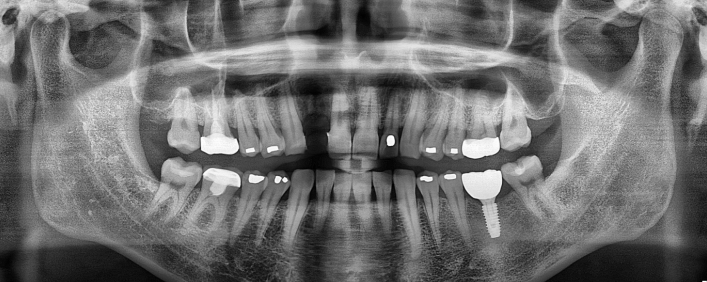

임플란트 치료사례

서울스마트치과는 결과로 증명합니다.

위 치료 사례는 서울스마트치과에서>직접 치료를 받고, 환자 본인의 동의를 얻어 게재된 사진으로 무단 인용, 도용, 재배포 시 민/형사상 책임을 질 수 있습니다.